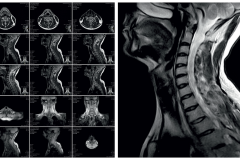

Polecamy też teksty poruszające klasyczne zagadnienia, jednak prezentujące nowe lub rozszerzone podejście do typowych problemów pacjentów. Należą do nich dolegliwości odcinka szyjnego, nerek, zmiany zwyrodnieniowe stawów kolanowych, a także dysfunkcja mięśni dna miednicy.